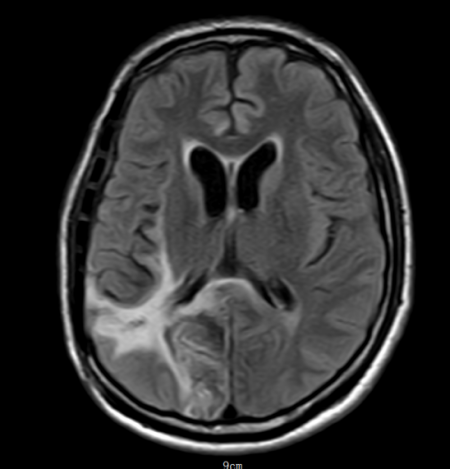

影像医学科王樱花主任阅片后,考虑脑脓肿合并急性脑疝。脑疝是颅内压增高最危险的并发症之一,堪称大脑“断电”前兆。当颅腔内某一部分压力骤增,脑组织被挤压到另一个腔室,压迫脑干,可迅速导致呼吸心跳停止。而脑脓肿是一种由细菌、真菌或寄生虫引起的颅内化脓性感染,若不及时处理,脓肿增大压迫脑干,后果不堪设想。

该患者MR显示:右侧顶枕叶类圆形低密度影,周围水肿明显,中线结构左移超过1cm脑室受压变窄,环池显示不清,提示小脑幕切迹疝早期,已处于濒死边缘。

术后第20天:神经功能明显恢复,患者可遵嘱动作,左侧肢体肌力恢复至Ⅲ级。